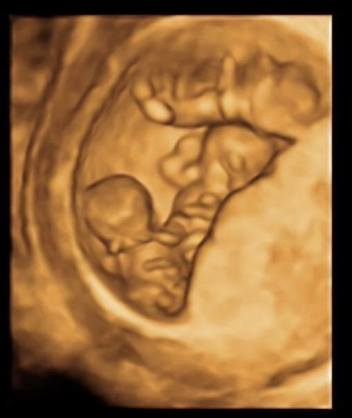

妊娠12周

這次竟然一下子來了個三胞胎